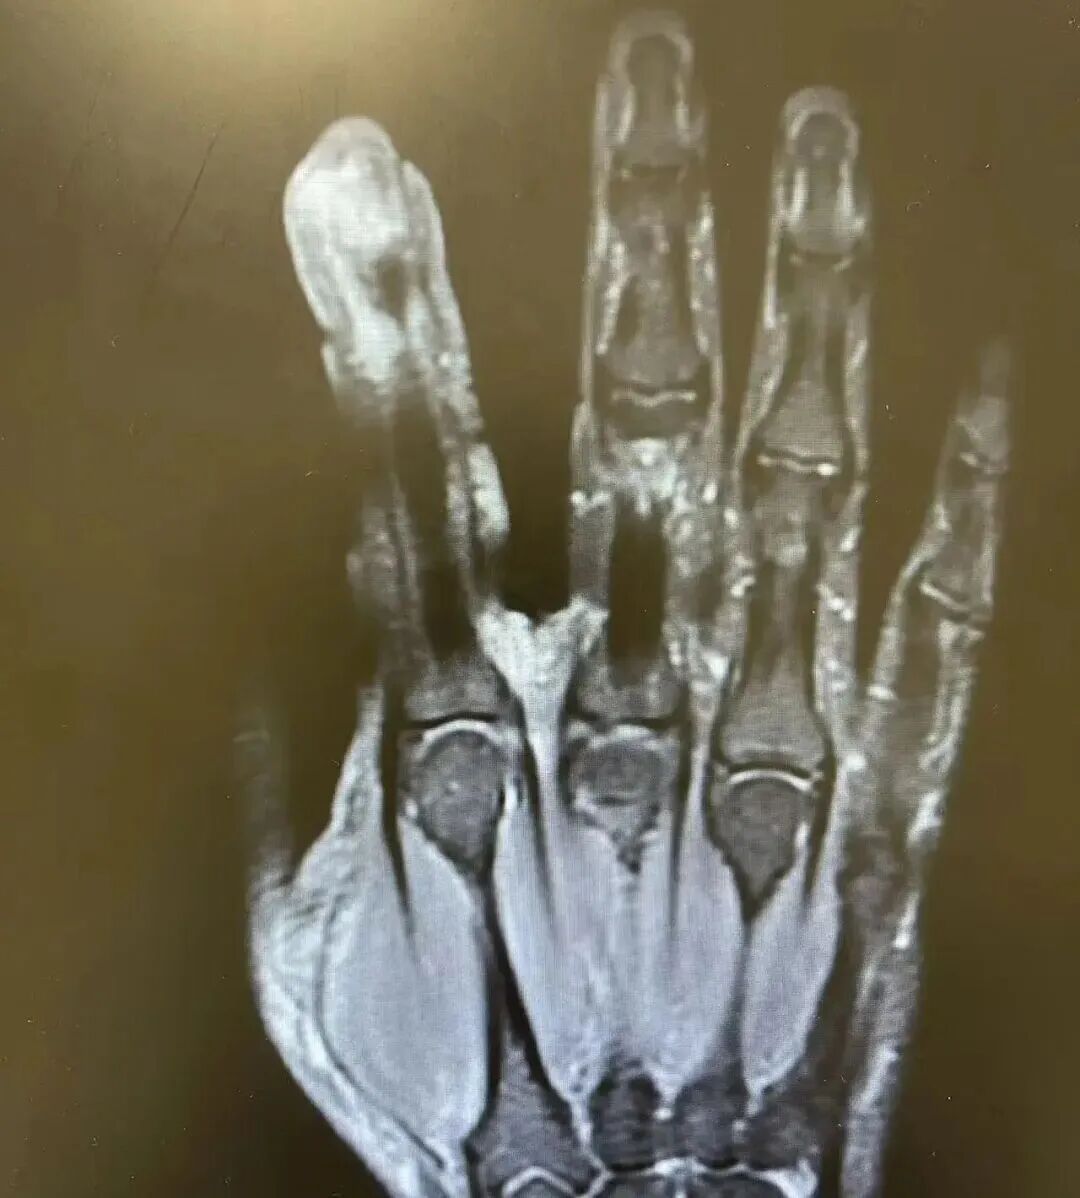

经检查,李大哥破溃的左手指尖严重感染,厌氧消化链球菌顺着破损处钻到骨头里,引发了严重骨髓炎。医生紧急手术,帮李大哥“刮掉”坏死的骨头碎片,清除了坏死的肌肉与皮肤。